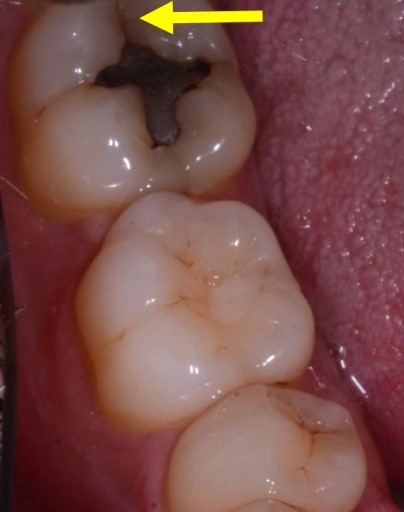

To bring this thought process into play on an actual case, let’s look at a case I had in my office. Preoperatively, the lower second molar had a relatively small failing alloy and looked to have a craze line over the mesial marginal ridge, as noted in the photo below.

There was also a more suspicious possible fracture, pictured below.